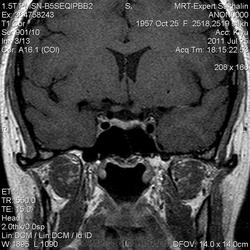

Как мы "динамичим"гипофиз

Женщина.6 лет назад выявлено образование левой доли нейрогипофиза.Пришла на контроль.

Постконтраст

Мне самой показался случай не совсем ясным, но динамик четко показывает участок с отставанием в контрастировании, воронка смещена вправо-о чем  думать бедному начинающему специалисту?